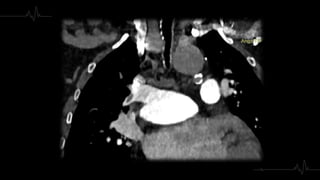

1. REPLECIÓN

Localización en el vaso

Morfología

Ángulo con respecto a la luz

2. TIPO DE TROMBO

Trombos Agudos

Localizados - centro

de la luz del vaso

Provocan dilatación Ocupan la totalidad de

la luz

Paso de contraste en

la periferia

Trombo rodeado de

contraste

(Signo de tranvía) Localización

excéntrica

Presentan ángulo

agudo con la luz del

vaso

Trombo Crónico

Defecto de

repleción completo

Disminución de

calibre y atrofia

vascular

repleción parcial

Localizarse en la

periferia del vaso

A veces son

concéntricos

Morfología de

banda lineal, red o

trombo mural

excéntrico

Calcificación del

trombo

Aumento de calibre

de las arterias

bronquiales y

colaterales

Menos frecuente

dilatación

segmentaria

bronquial

Localización en elvaso Morfología Ángulo con respecto a la luz 2. TIPO DE TROMBO

Trombos Agudos Localizados -centro de la luz del vaso Provocan dilatación Ocupan la totalidad de la luz Paso de contraste en la periferia Trombo rodeado de contraste (Signo de tranvía) Localización excéntrica Presentan ángulo agudo con la luz del vaso

Trombo Crónico Defecto de replecióncompleto Disminución de calibre y atrofia vascular Defecto de repleción parcial Localizarse en la periferia del vaso A veces son concéntricos Morfología de banda lineal, red o trombo mural excéntrico Calcificación del trombo Aumento de calibre de las arterias bronquiales y colaterales Menos frecuente dilatación segmentaria bronquial